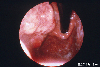

조기위암 0-I형 (I)

위체상부에 보여지고, 점막하층에 다량으로 침윤한 I형의 조기위암